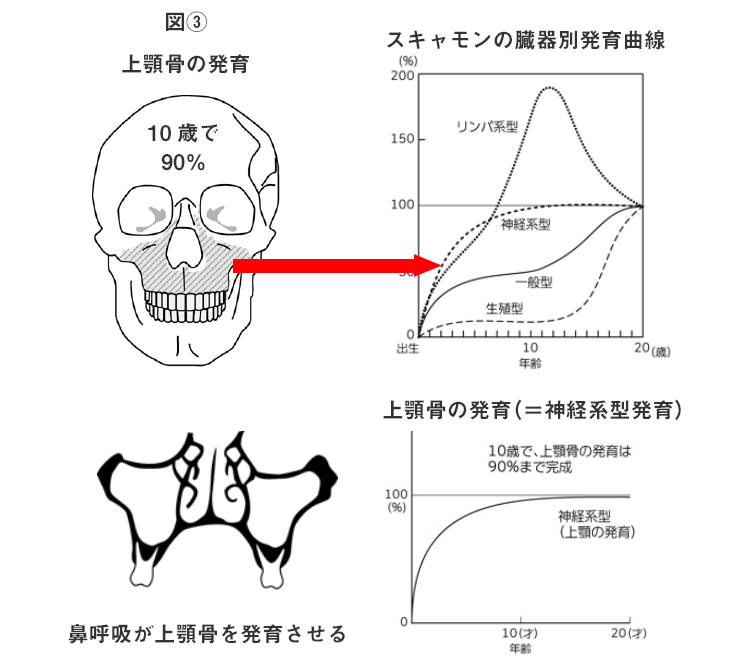

私たちは、図③に指すごとく、上顎骨の発育の90%は10才前後で終了し、その後は、あまり発育しない事を一般の保護者の方に知って頂きたいと思っています。

しかも、その発育には、鼻呼吸が大変重要なのです。